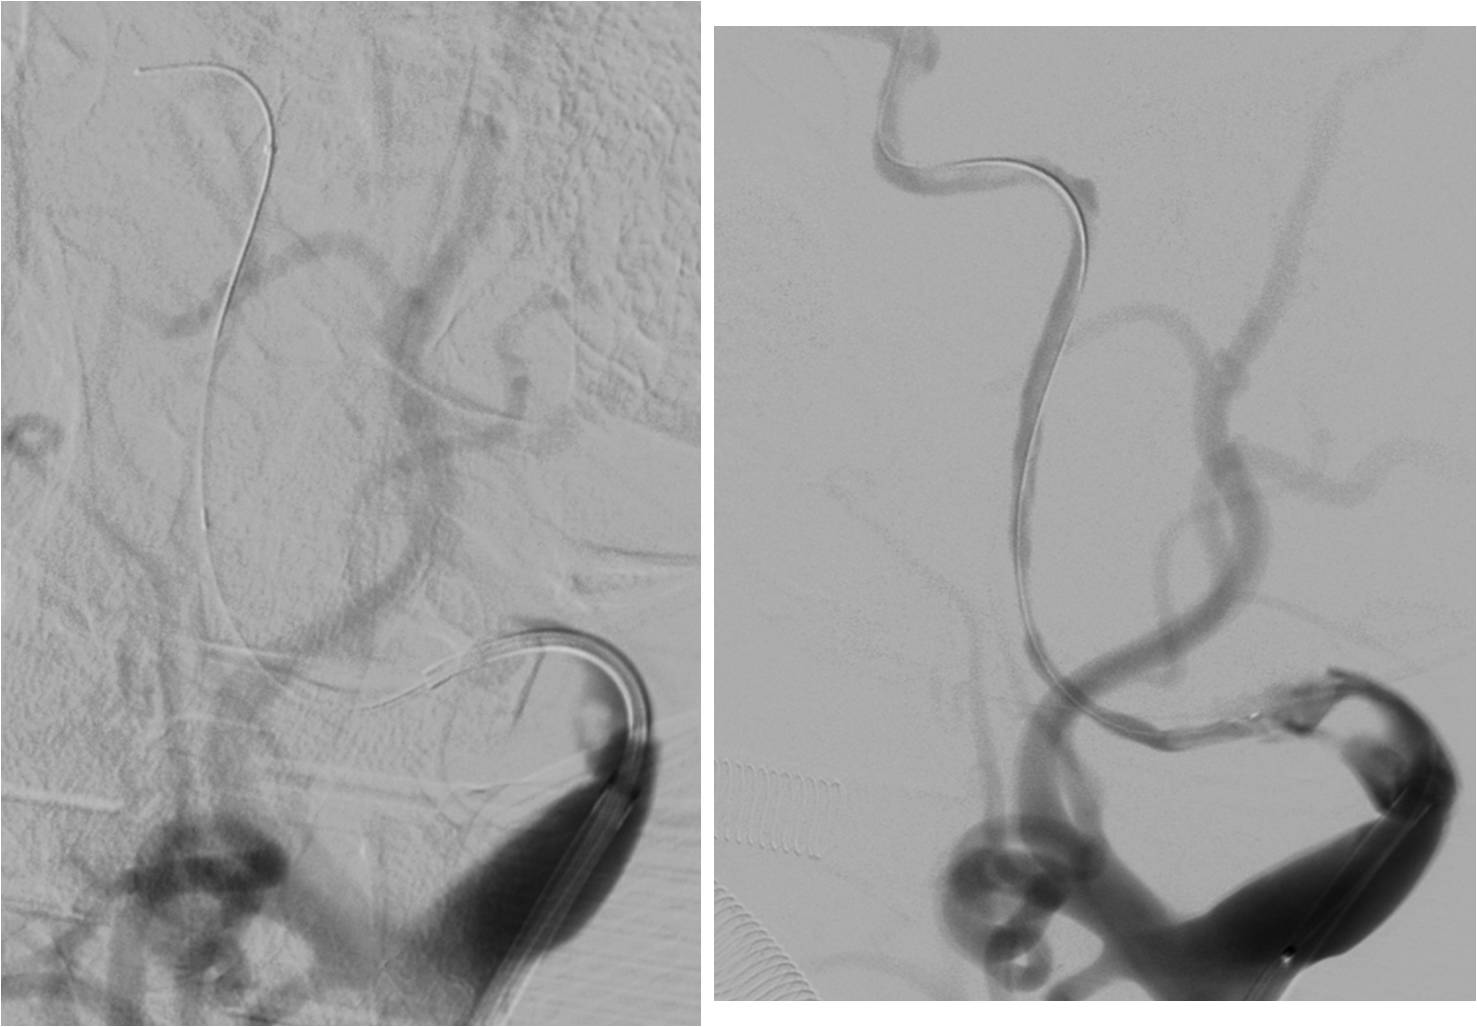

》全麻下手术

》术后C臂CT无出血

》术后20小时复查头颅CT无出血。